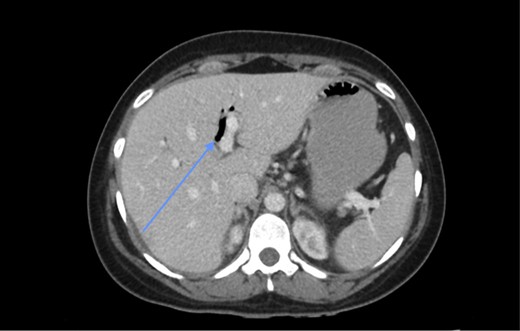

Laboratory investigations (biochemical profile and urinalysis) were all within normal limits. Abdominal CT showed pneumobilia and a 2 cm intraluminal density in the distal ileum with resultant small bowel obstruction (Figs 1 and 2). She underwent emergency laparotomy and enterolithotomy followed by a smooth postoperative course (Figs 3 and 4). The CT scan taken elsewhere and just prior to the emergency cholecystecomy 12 months earlier was reviewed; this demonstrated a markedly distended gallbladder with irregular wall thickening and severe pericholecystic fat stranding consistent with a gallbladder empyema measuring 16 cm × 9.0 cm. There were also multiple gallstones with the largest two measuring 2 cm at the neck of the gallbladder and the other, 2.0 cm in diameter at the fundus of the gallbladder, respectively. There was a narrower, septum-like area between the neck and grossly distended empyema (Fig. 5)

CT scan showing a rim-calcified gallstone, causing ileal obstruction.